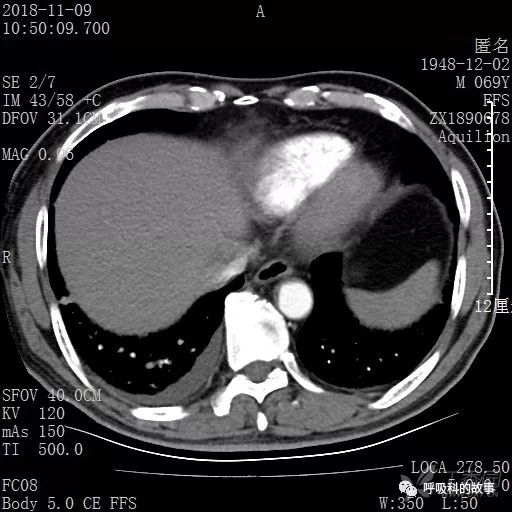

胸部增强CT示右肺门占位伴远端阻塞性肺炎,纵膈、右肺门、右侧颈根部、右侧腋下及肝门部肿大淋巴结。两侧胸腔少量积液。

纵隔窗的增强CT